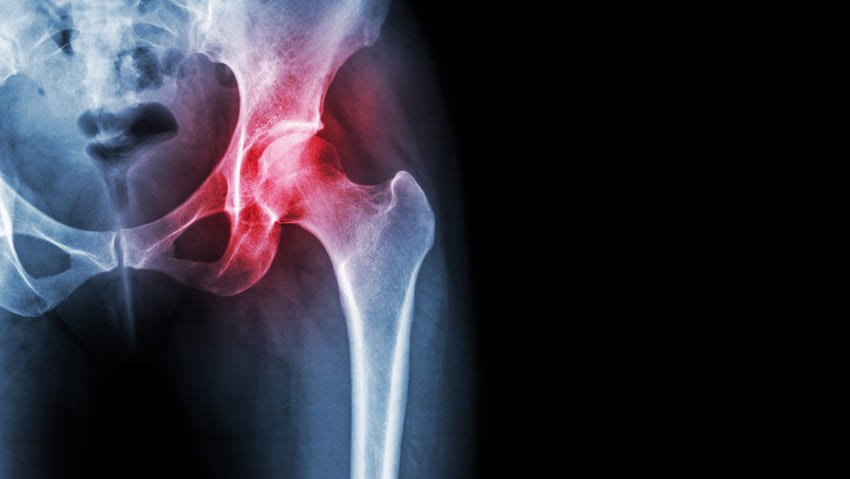

Vilka tillstånd behandlas vanligen med höftledsplastik?

Total höftplastik används vanligen för att behandla:

- Ledfel orsakat av artros.

- Reumatoid artrit

- Traumatisk artrit

- Höftfrakturer

- Avaskulär nekros

- Godartade och elakartade bentumörer och andra mindre vanliga tillstånd